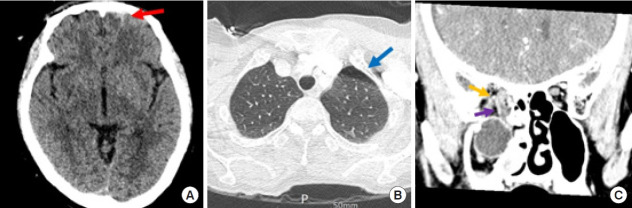

Orbital floor fractures are commonly encountered, but the dislocation of the eyeball into the maxillary sinus is relatively rare. When it does occur, globe dislocation can have serious consequences, including vision loss, enucleation, and orbito-ocular deformity. Immediate surgical intervention is typically attempted when possible. However, severe comorbidities and poor general health can delay necessary surgery. In this report, we present the surgical outcomes of a 70-year-old woman who received delayed treatment for traumatic eyeball dislocation into the maxillary sinus due to a subarachnoid hemorrhage and hemopneumothorax. Additionally, we propose a treatment algorithm based on our clinical experience and a review of the literature.